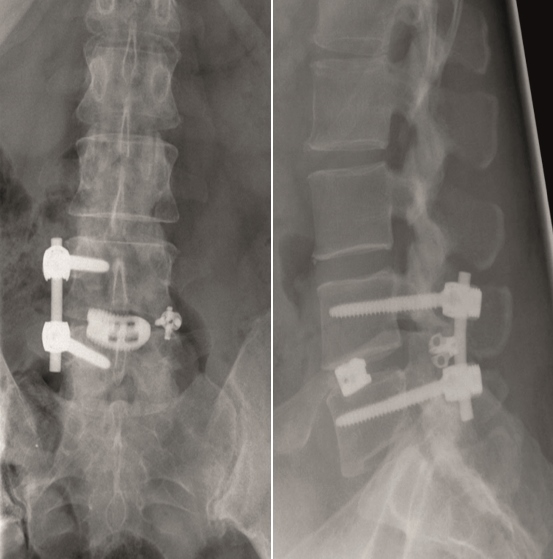

Multilevel facet pathology is shown in Fig 6. Intraoperative and postoperative images are shown (Fig 7-9).

Case 2